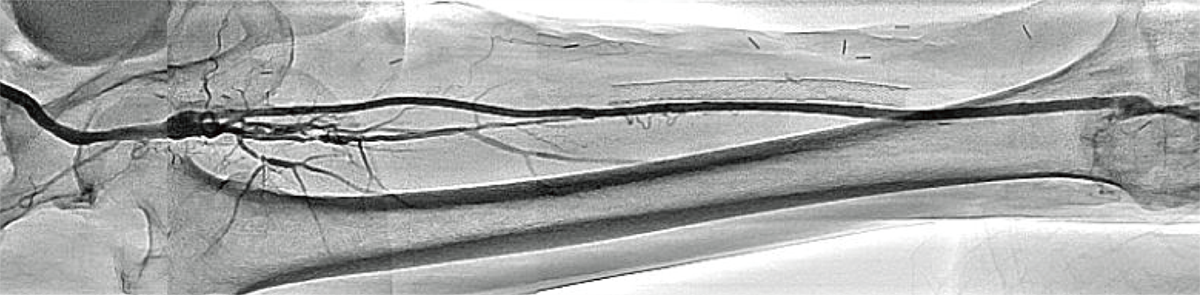

Dynamic Trace (DT)

Dynamic Trace дає клініцистам можливість виконувати цифрову зйомку під час руху стола за потоком контрасту. Це зображення є прикладом панорамування від стегна до стопи

DT – це цифровий метод отримання даних, який використовується в режимі панорамування для покращення зображення судин за рахунок збільшення стиснення фону та зменшення візуалізації кісток. Ефект, схожий на DSA.